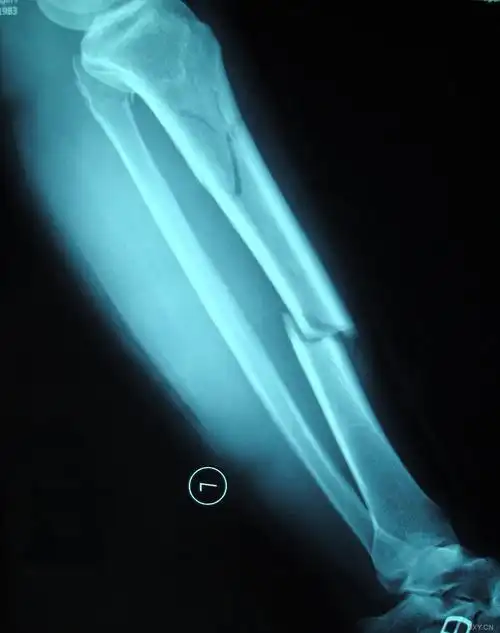

术前左小腿x线如下